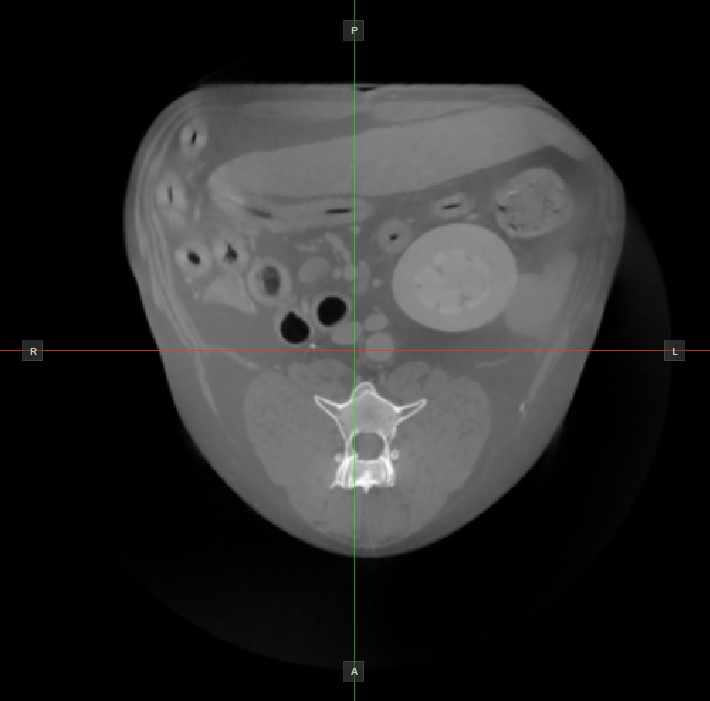

Cursor and Cross Center Position

When working with CT modality volumetric DICOM data, the HU (Hounsfield Unit) values of each pixel in the 3D body is of great importance. Hounsfield Unit is a quantitative scale used to measure the radiodensity of each tissue.

Move the mouse cursor over the images in each of the three available planes to read out the HU value in that specific cursor position. If the cursor is not within the bounds of the image, the cross center position of the intersection between the two slicers and its HU value is shown.

../../_images/image230.jpg ../../_images/image52.jpg

Image Orientation and Image Planes

The position and intersection of the other two image planes not represented in the active viewport is indicated by two vertical and horizontal lines called slicers. The endpoints of each slicer are labeled with a letter that corresponds to the appropriate direction/side of the 3D volume, based on the RAS coordinate system.

Only four sides of the available six are indicated on each 2D viewport. The labels and the corresponding side are the following:

• Patient Right (R), indicating the right side of the body

• Patient Left (L), indicating the left side of the body

• Anterior (A), indicating the front side of the body

• Posterior (P), indicating the back side of the body

• Superior (S), indicating the top side of the body

• Inferior (I), indicating the bottom side of the body

../../_images/image323.jpg ../../_images/image19.jpg ../../_images/image286.jpg